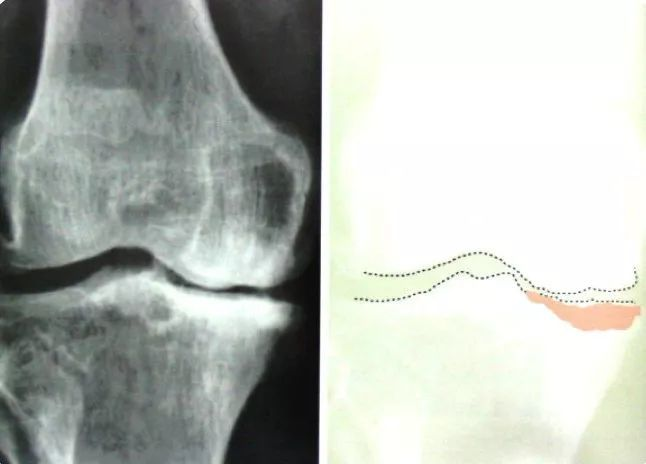

如果您自己的關節有以上的癥狀,活動后會加重,休息后可以部分緩解,那就要考慮您可能得了骨性關節炎了。這時就需要到醫院做一個X線片來進一步明確診斷。